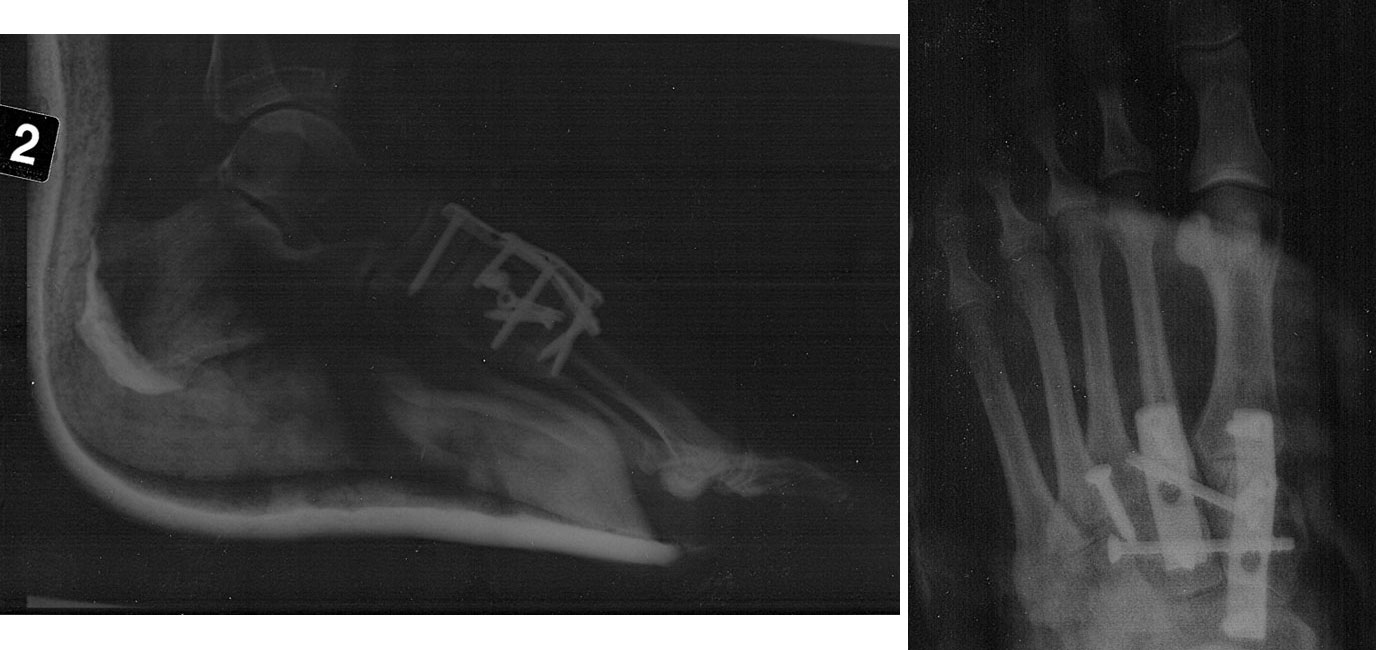

Zara was out of action for about eight months with a broken foot sustained at the 2007 3rd round ISA event in Namibia. She crashed at about 37 knots but unluckily her left foot stuck in the footstrap as she fell forward. Resulting in a break and dislocation of four bones in her left foot. She Is back in the UK now and has had two operations to fix the foot, but it going to be a long recovery. But those that know Zara well will know she will work hard and be back on the water as soon as possible.

Click picture

to see more gory detail!